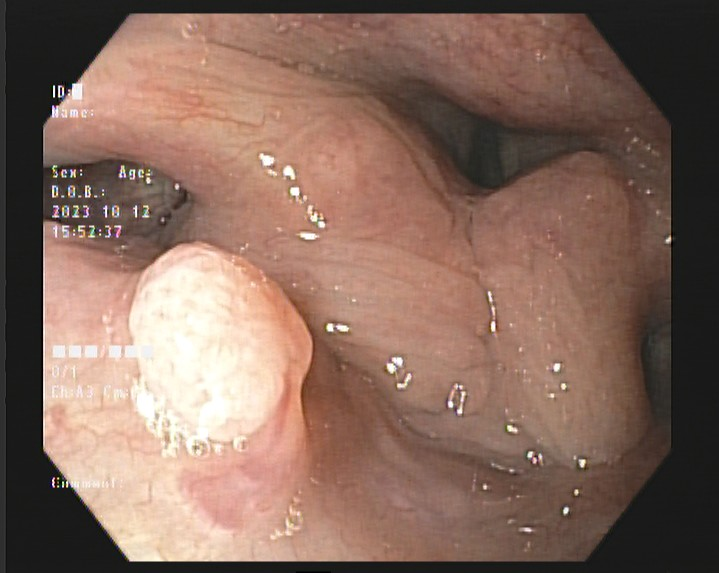

结肠良性肿瘤

结肠腺瘤